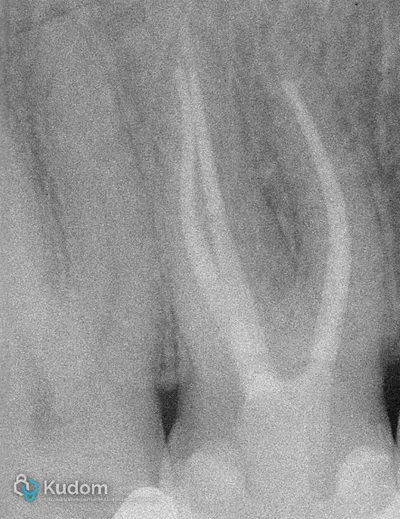

Ritrattamento endodontico complesso di un primo molare inferiore con lesione alla forcazione e otturazione di un canale laterale con successivo build-up per overlay a ricopertura cuspidale.